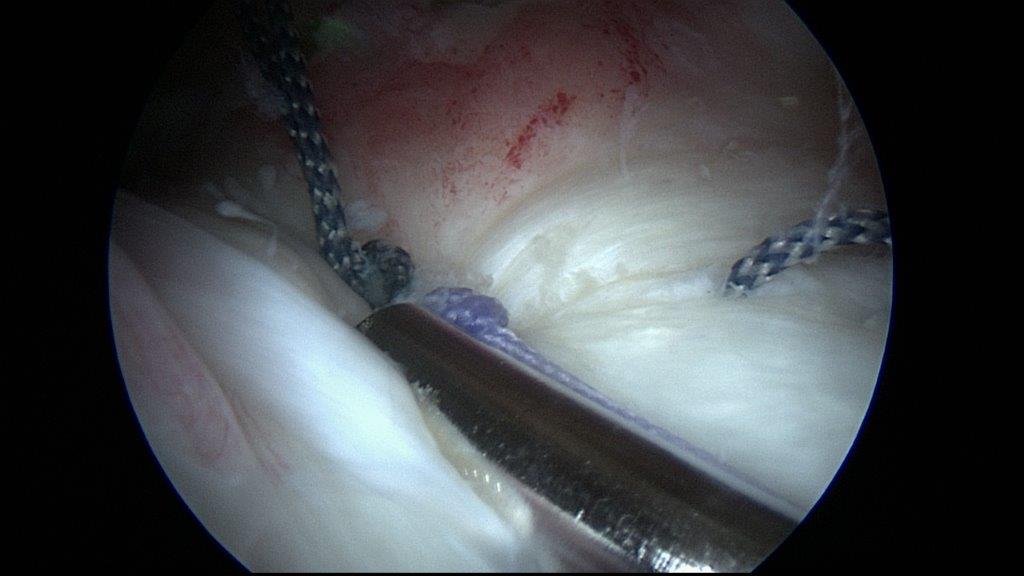

• Arthroskopische Sehnenrekonstruktion „ Schlüsselloch-Chirurgie“

Die Operation in und um das Gelenk wird über kleine Inzisionen von ca. 1 cm mit Hilfe einer dünnen Stabkamera in Videotechnik durchgeführt. Das Gelenk wird mit Wasser aufgefüllt und über weitere kleine Inzisionen werden Instrumente in das Operationsfeld gebracht.

Nähen des Risses während der Arthroskopie